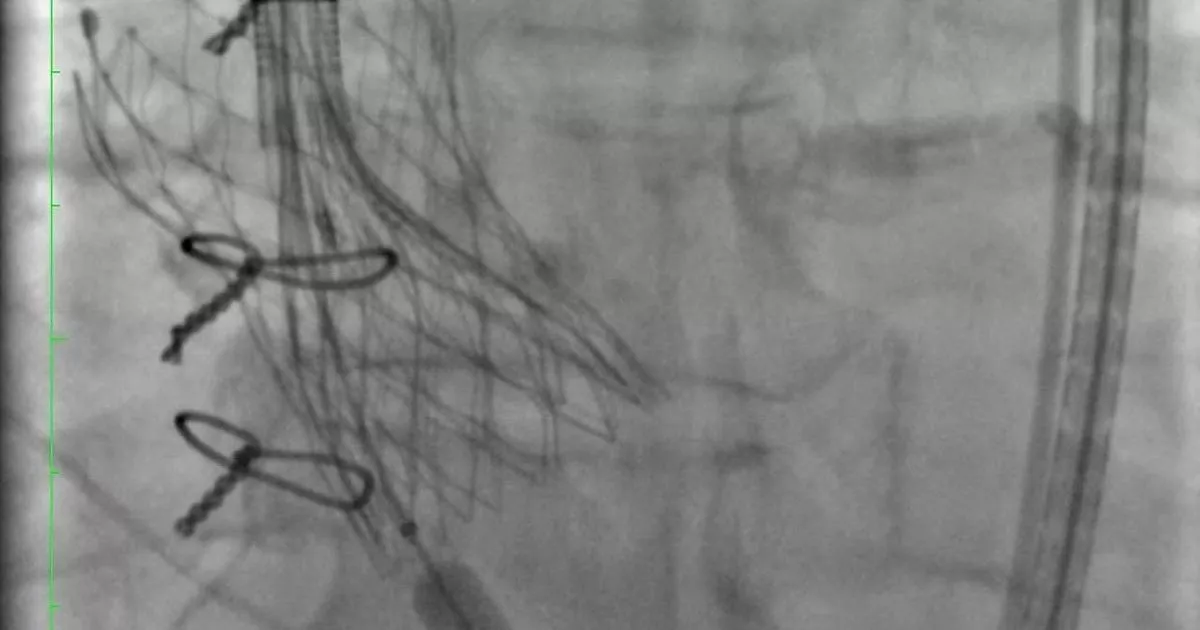

Врачи НИИ-Краевой клинической больницы №1 (НИИ-ККБ №1) много лет проводят операции по транскатетерной имплантации аортального клапана. Их делают через прокол в ноге, без наркоза. Но у протеза ограниченный срок службы – 10 лет. Потом он обрастает кальцием, и пациенту вновь нужна операция.

– Когда старый клапан уже износился, в этот же протез клапана ставится новый – методика «клапан-в-клапан» или по-простому говоря – по типу «матрешки». Недавно мы провели первую подобную операцию 70-летнему мужчине, вставив в старый изношенный протез аортального клапана новый клапан, – рассказал завотделением рентгенхирургических методов диагностики и лечения НИИ-ККБ №1 Алексей Федорченко.

Операция проводится малоинвазивным методом, что сокращает время реабилитации пациента и позволяет ему уже спустя пару дней вернуться к привычному распорядку жизни. Так, пенсионер скоро займется любимым хобби – рыбалкой.